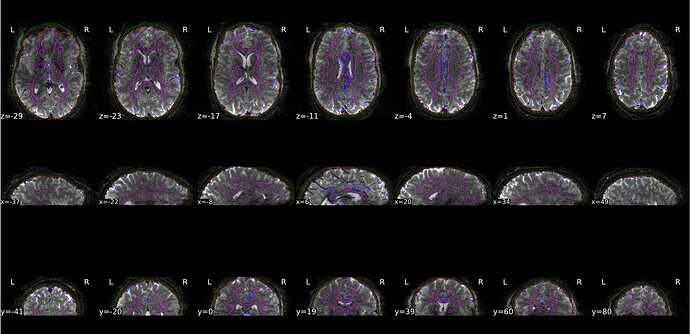

Here is a screenshot from the HTML report (‘Brain mask and (anatomical/temporal) CompCor ROIs’ section) where there is no stretching outside of the FoV of the EPI: